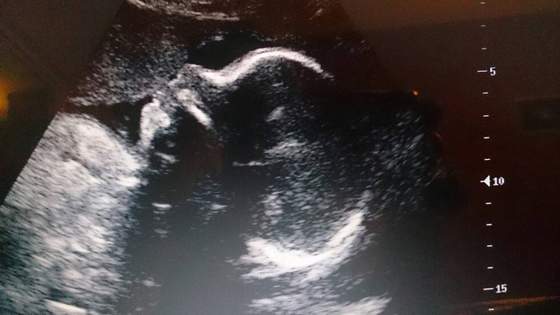

No my już po.

Z młodą wszystko dobrze, waży już 1455g :-D

Szyjka długa 4cm, łożysko na przedniej ścianie, wody w normie :-)

No i w końcu pokazała trochę buźki :-D